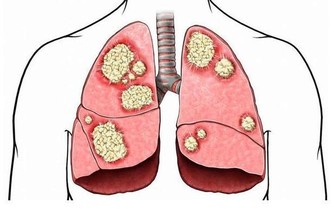

5、頭暈、乏力、嗜睡: 甲醛可影響人的造血系統,輕則引發貧血,嚴重的甚至可能導致白血病。有調查指出,醫院血液科病房中三成以上白血病患者的家庭在兩年內進行過裝修。而兒童因裝修患病的機率更高,佔患病兒童的半數以上。當人體血液供應不足時,就會經常感到疲憊,走路都沒有力氣。因此,入住新居後有頭暈、乏力、嗜睡的症狀,應及時去醫院檢查血常規。